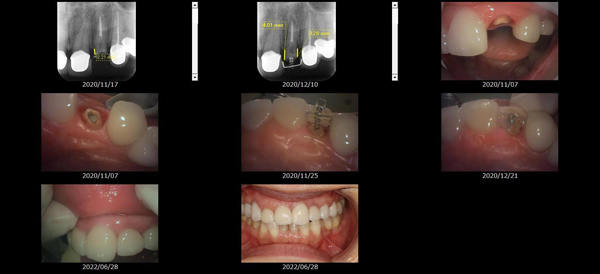

救歯MTM

虫歯が大きくて残せない歯、転倒などの事故により歯が根の深いとこで折れてしまったなどで、抜かざるを得ない歯を、骨の中に埋まっている健全な根を、骨の上に矯正的に引き上げることで、その歯を抜かず温存、救歯できる可能性のある治療方法です。

①健全な歯を、歯肉から見える位置にまで引き上げることで

根の治療の成功率を上げることが出来る。唾液には沢山の細菌がいます。唾液が入らない環境での根の治療を(神経の治療)を行うことで神経の治療、根の治療の成功率は格段と上がります。

②骨の上にある歯と土台で支える被せもの製作できる。

被せものを土台だけに頼ることなく、引き上げた健全な歯でも支えることで、歯への被せ物がしっかりと装着できるようになる。

③抜かずに歯を活かすことで、隣の歯を削るブリッジやインプラントにしないで済むことがある。

歯を矯正的に引き上げることで、その歯を救歯できるだけでなく、隣の歯を削るなどの侵襲を回避できる場合がある。

救歯治療と審美性の両立

当院では様々な治療の基礎に審美と機能の両立というテーマがあります。

- > 歯を矯正的に引き上げることで、骨の中の根の長さは短くなりますが、その短さでも安定するという診断をした場合のみ施術になります。 残せる歯、根の長さが短い場合は、この救歯MTMの治療対象とならない場合がございます。

- > 治療期間が数か月~1年に及ぶ場合がある。

- > 費用が自費診療 44,000円 ~ 66,000円

- > 救歯MTMは救歯BTAセラミックと併用治療が必要な場合があります。

症例